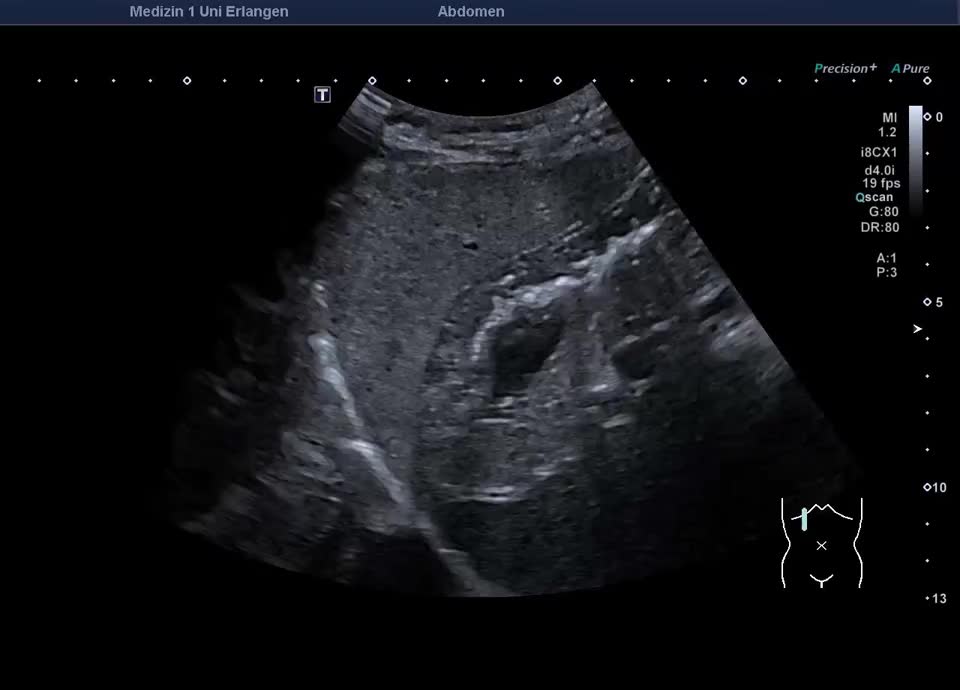

Rekanalisierte Umbilikalvene bei dekompensierter Leberzirrhose mit Aszites, siehe auch Folgevideo

Rekanalisierte Umbilikalvene bei dekompensierter Leberzirrhose mit Aszites (vergleiche auch vorheriges Bild)